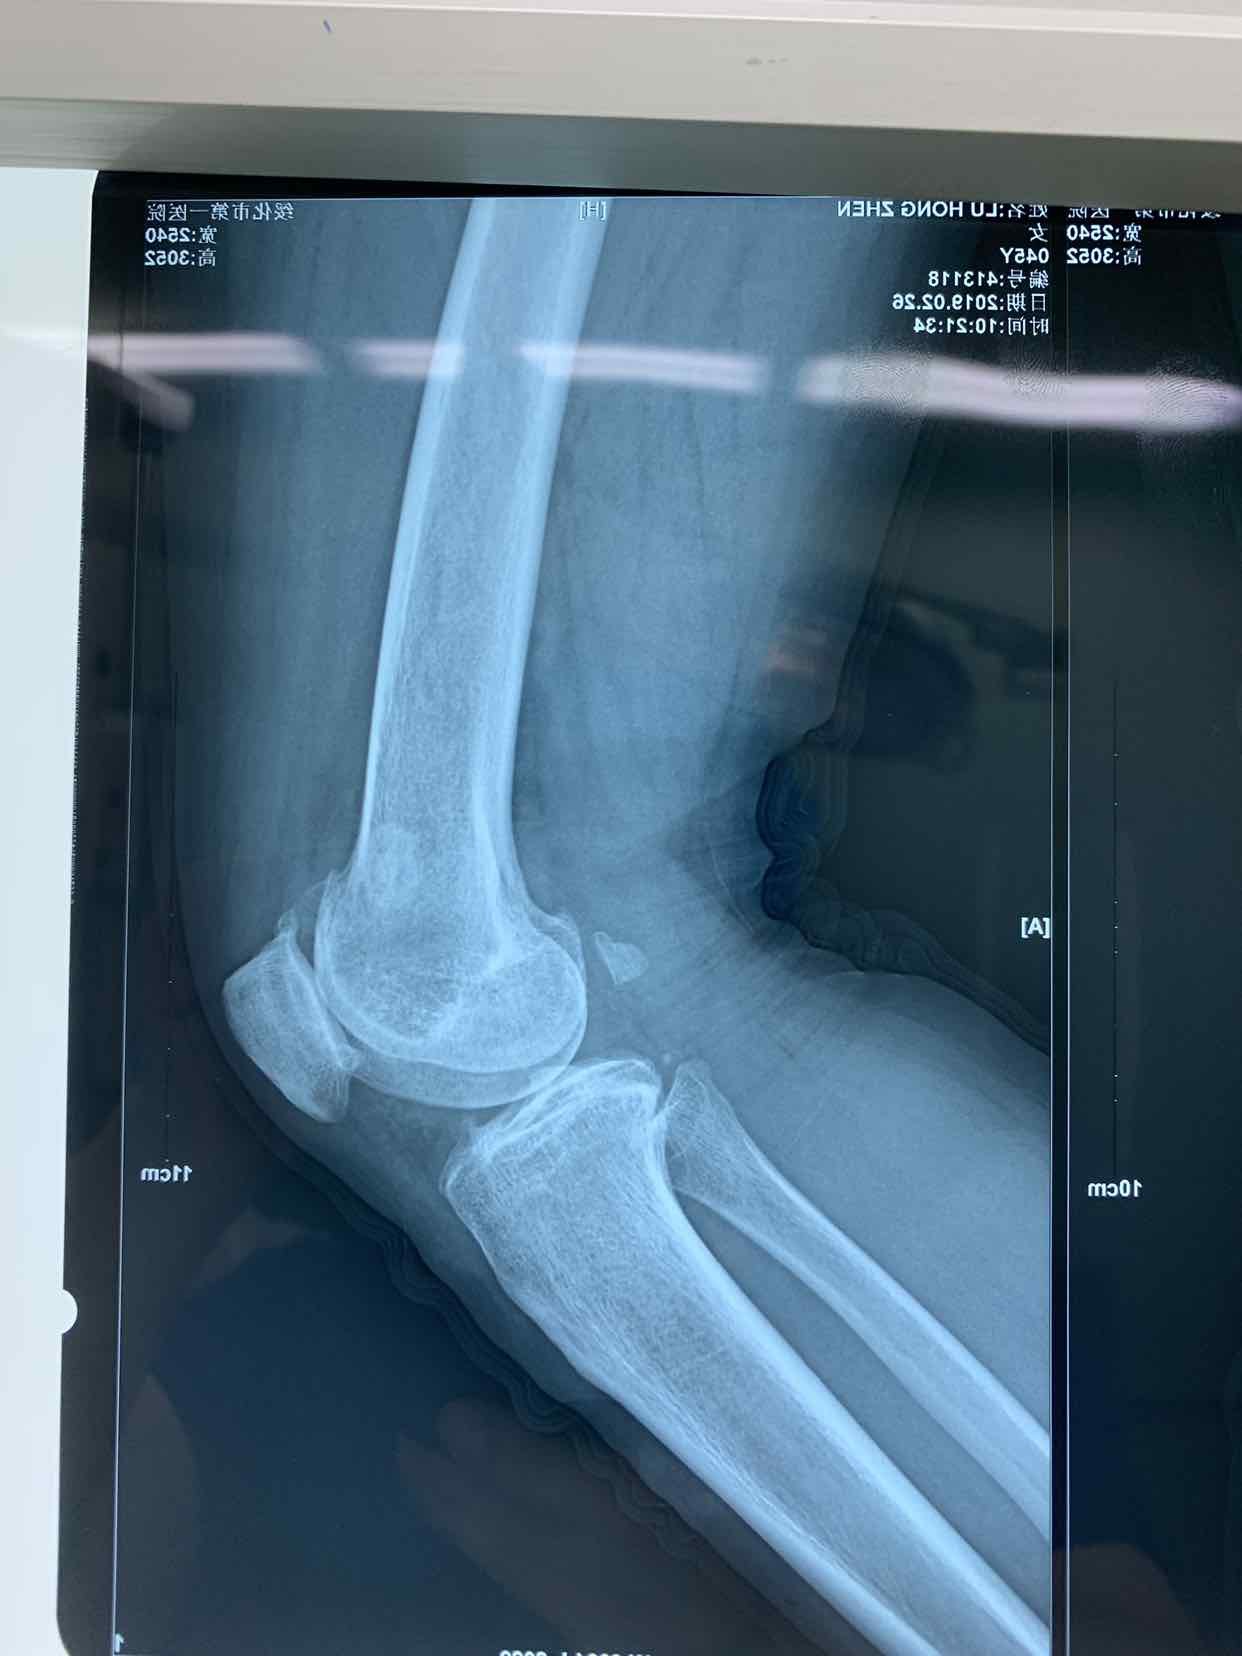

患者因双侧膝关节骨性肿物发现二十余年。收入院。患者无二十余年前无明显诱因发现双侧膝关节内有骨性肿物。异常活动。偶尔在屈曲活动时出现局部嵌夹于关节内。疼痛。不能活动。并弹响。近半年内肿物增大。疼痛发作频繁。遂来诊。门诊拍片提示见双侧膝关节内骨性游离体,位于关节内。门诊以双侧膝关节游离体收入院。

查体见患者双侧膝关节局部肿胀。压痛。可于局部触及骨性肿物在关节内游走。屈伸活动时偶有嵌顿。行走活动受限。拍片提示双侧膝关节骨性游离体。